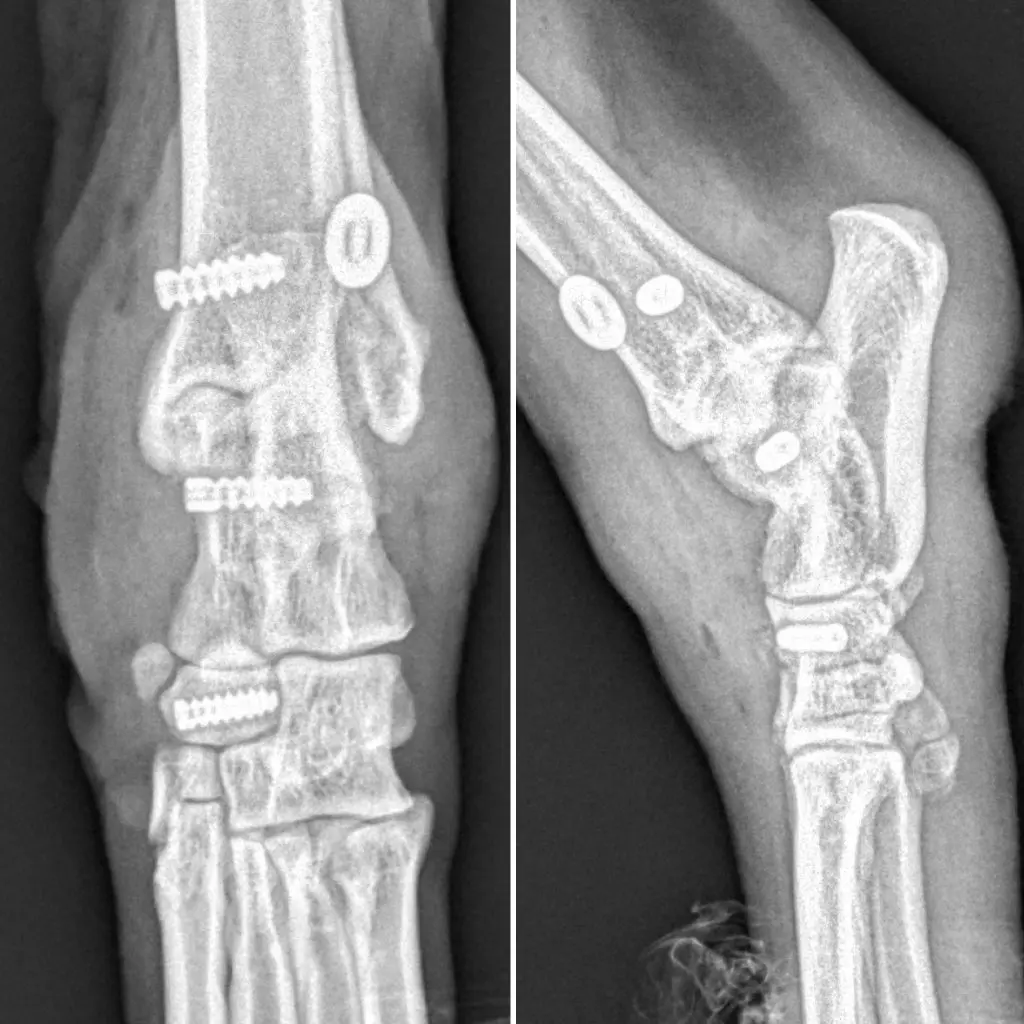

Al finalizar el procedimiento y cerrar el abordaje quirúrgico por planos, comprobamos radiológicamente la correcta ubicación de los implantes, así como la estabilidad definitiva de la articulación, tanto en flexión como en extensión.